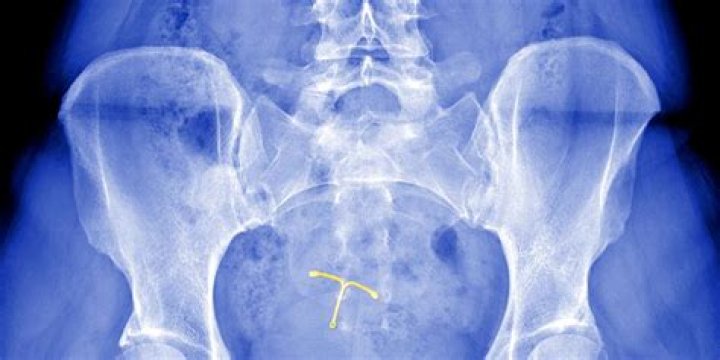

Mirena lawsuits accuse Bayer Pharmaceuticals of hiding side effects and making a defective intrauterine uterine device (IUD). Women blame the birth control device for organ perforation, dislodging from the uterus and causing pressure buildup in the skull.